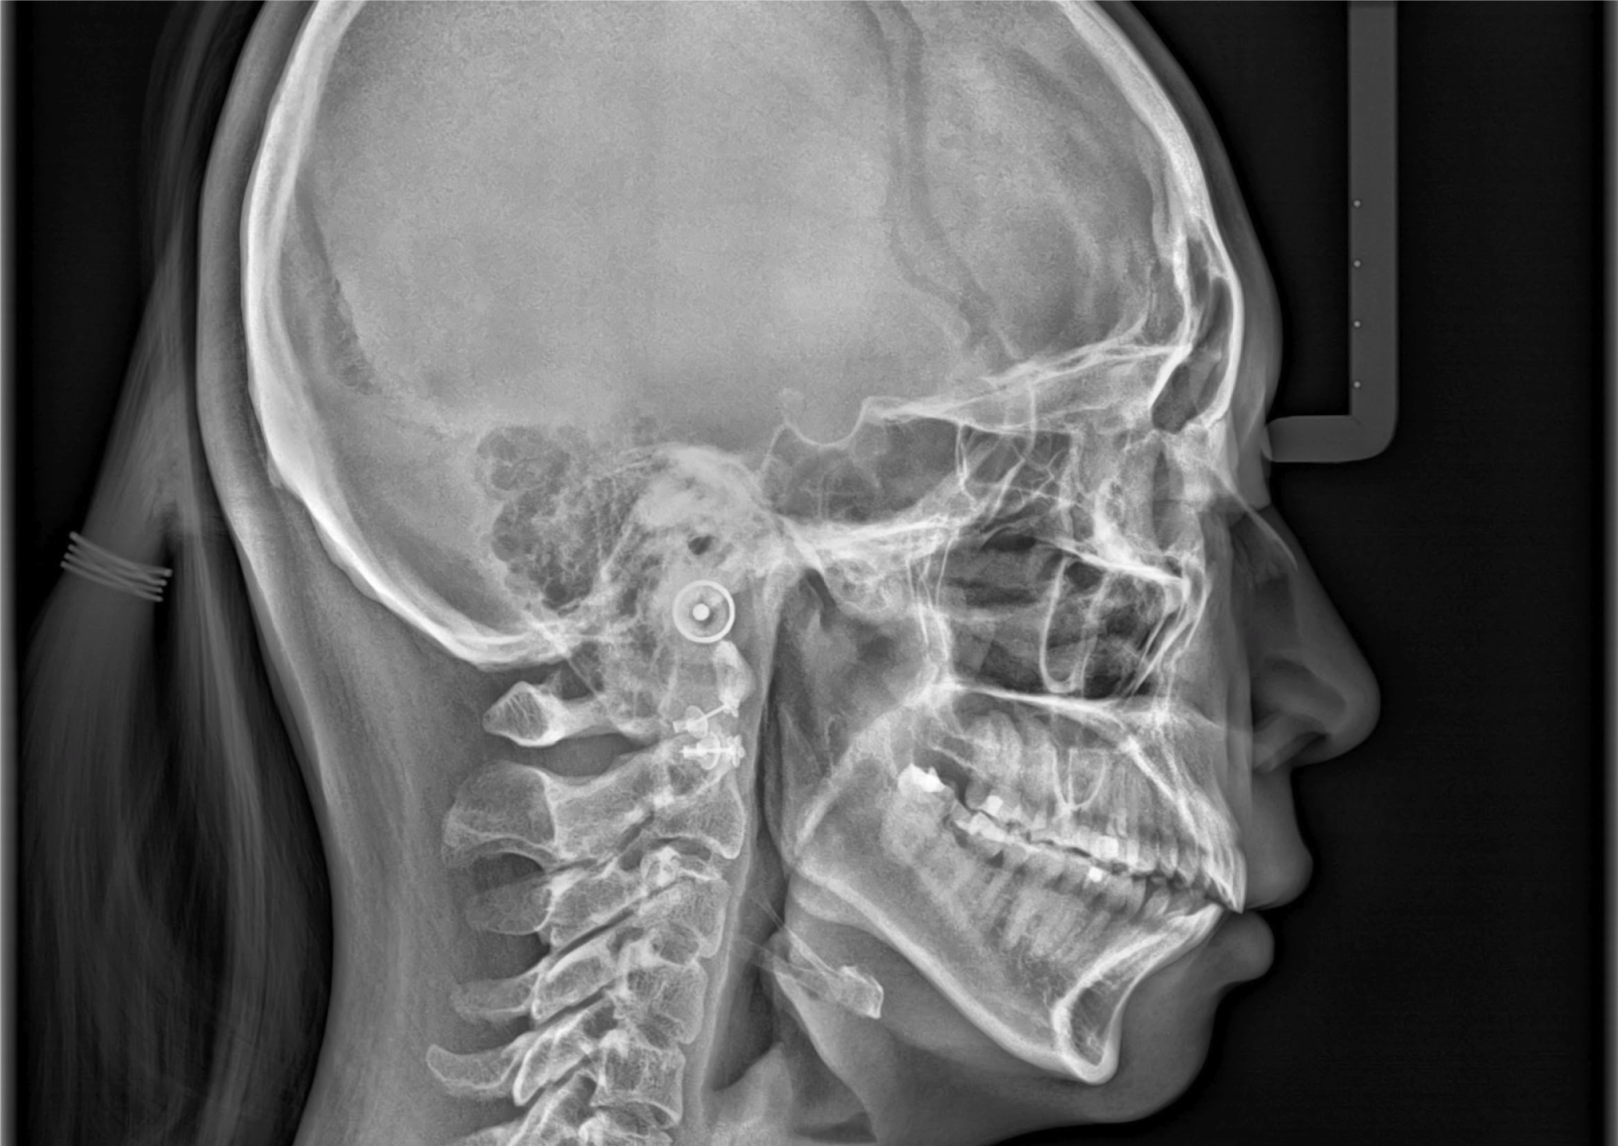

2D Imaging Evaluation

Often a Panoramic or PA radiograph gives us a wealth of information without additional exposure to the patient. We review these images, for new patients or follow ups, and provide detailed information that will help you improve the patient experience.